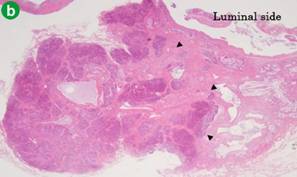

Macroscopically, diffuse thickening of the gallbladder wall and nodular thickening (7 mm in diameter) was observed near the cystic duct (Figure 3a). Histopathological examination revealed pancreatic acini and ducts without islets of Langerhans inside the nodular lesion and diffuse hyperplastic cholecystopathy (Figure 3bc). Based on these findings, the case was histologically diagnosed as adenomyomatosis and heterotopic pancreas in the gallbladder wall. We routinely measured the constituent of the bile in the resected gallbladder. We detected elevated amylase and lipase levels of 6,372 IU/L and 9,144 IU/L, respectively, compared to median levels of 24 IU/L and 246 IU/L, respectively, at the presenting in our hospital. For reference, the mean levels of amylase and lipase in bile in patients with pancreaticobiliary maljunction are 127,901 IU/L and 222,692 IU/L, respectively, in our hospital.

Figure 3. Image of protruding lesion near the cystic duct (a. arrow). The microscopy reveals pancreatic acinar and duct content in the layer of subserosa (b. H&E, x100; c. H&E, x400). |